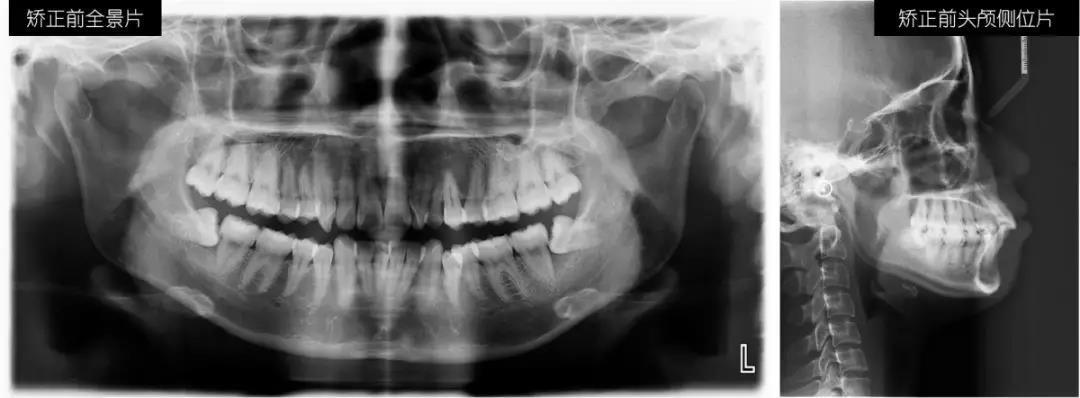

戴時代天使牙套前,我分了兩次拔了下排左右2顆多余的智齒,還確認了時代天使3D動畫設(shè)計方案,直觀地看到,在即將到來的日子里,我的牙齒是如何通過片切留出移動排齊的空間,如何一步步移動到理想狀態(tài)。